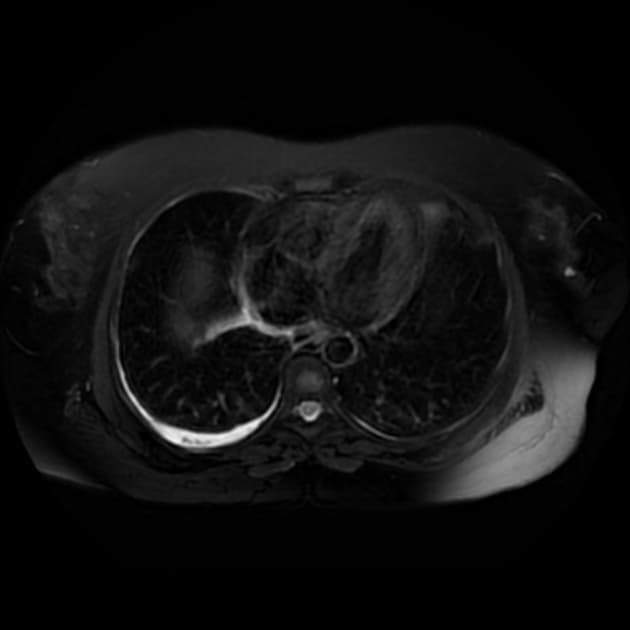

Axial FIESTA FS

- Túi mật chứa nhiều viên sỏi, được hiển thị rõ trên các chuỗi xung MRI khác nhau.

- Các sỏi được xác định rõ nhất trên hình ảnh trọng T2 và MRCP do chúng hiện lên như các vùng giảm tín hiệu (hypointense) trong lòng túi mật.

- Hình ảnh trọng T2 và MRCP là các kỹ thuật hình ảnh lý tưởng để phát hiện sỏi túi mật và sỏi ống mật do đặc tính không tín hiệu (no signal) của sỏi trên các chuỗi xung này.

Sỏi túi mật, hay còn gọi là cholelithiasis, thường được phát hiện tình cờ hoặc ở bệnh nhân có các triệu chứng như đau quặn mật hoặc rối loạn tiêu hóa. MRCP là phương tiện hình ảnh không xâm lấn, hiệu quả cao, sử dụng các chuỗi xung trọng T2 để hiển thị dịch đứng yên trong hệ thống đường mật. Các viên sỏi hiện lên như những khuyết thiếu tín hiệu giảm đậm độ rõ ràng trong lòng túi mật hoặc ống mật. Khác với siêu âm, MRCP cung cấp hình ảnh rõ nét toàn bộ hệ thống đường mật, kể cả đoạn cuối ống mật chủ, mà không bị ảnh hưởng bởi hơi ruột hay thể trạng bệnh nhân. MRCP không cần thuốc cản quang hay tia bức xạ, do đó rất phù hợp để đánh giá các bệnh lý đường mật nghi ngờ khi siêu âm không kết luận được. Tuy nhiên, MRCP không đánh giá được chức năng túi mật hay tình trạng viêm thành túi mật, nên việc kết hợp với lâm sàng là cần thiết.